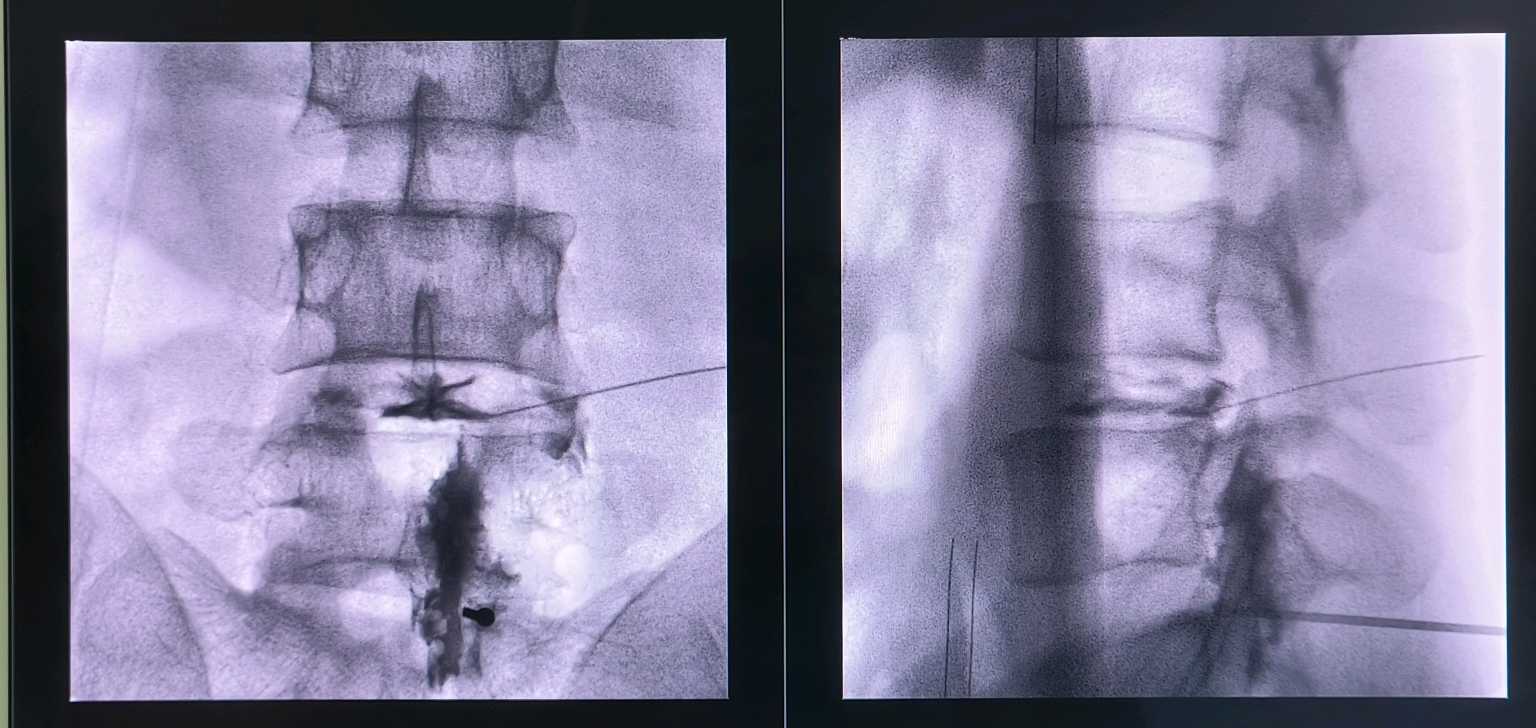

有,胶原酶技术是个古老而又新兴的技术,胶原酶可以水解突出的椎间盘,变成水和氨基酸,更绿色,更微创,无痛苦,可以说是一根针一个针眼解决椎间盘突出

问题,不开刀,临床疗效不差于开放手术!